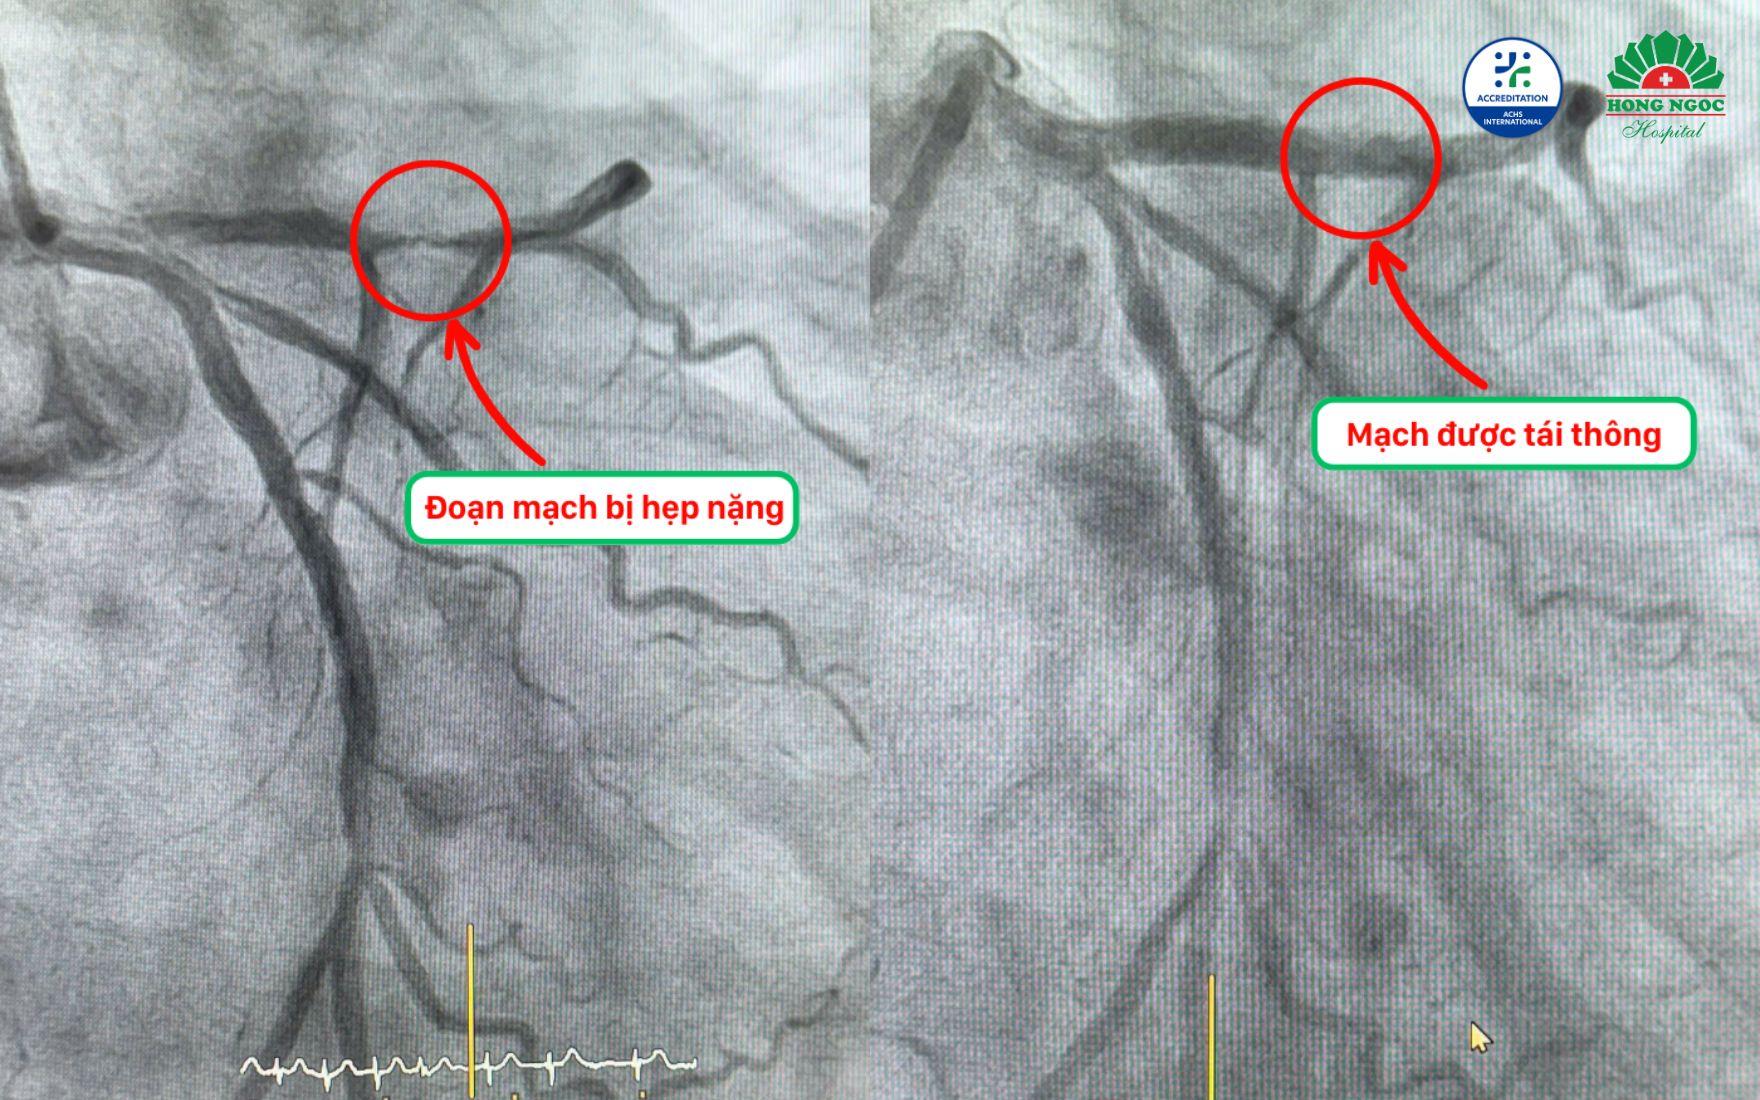

Kết quả chụp mạch vành cho thấy bệnh nhân bị tắc gần như hoàn toàn đoạn đầu động mạch liên thất trước - nhánh động mạch nuôi tim chính. Ngoài ra, động mạch vành phải cũng bị hẹp khoảng 70%, làm tăng nguy cơ thiếu máu lan tỏa. Với tình trạng tổn thương đa nhánh, ê kíp quyết định can thiệp bằng cách đặt 1 stent phủ thuốc tại vị trí động mạch liên thất trước, sử dụng kích thước phù hợp với lòng mạch và kiểm soát chặt chẽ áp lực nong bóng - vừa mở rộng dòng chảy, vừa hạn chế tổn thương thành mạch, đặc biệt ở bệnh nhân có nguy cơ chảy máu cao như ông Chiến.

Hình ảnh mạch vành trước và sau can thiệp của bệnh nhân